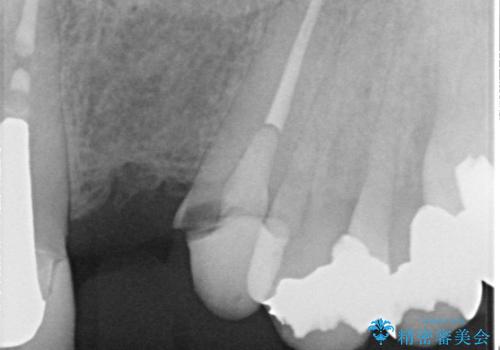

左上1番目~3番目にかけてブリッジの仮歯が入った状態で来院された患者さんで、左上3に縁下カリエスを認め抜歯してインプラントか牽引(エクストリュージョン)を行うか、歯肉根尖側移動術を行うか選択いただき牽引の後補綴処置を行うこととしました。

左上3の牽引を1か月半ほど行った後、補綴治療を行っています。

両支台歯とも根尖病巣は認められなかったため、ファイバ-コアからのやり替えとしました。